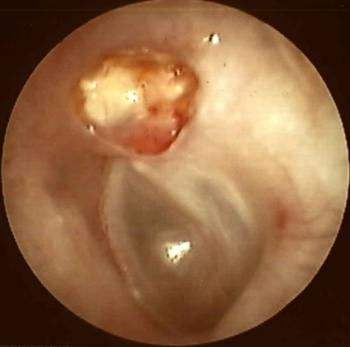

罹患急性中耳炎常会有下列症状,象是快速且突然的发病,或是中耳有积液的情况,造成耳膜肿胀突出,导致听不清楚甚至流脓。以及中耳有发炎反应,如耳膜发红、耳痛都是常见的情形。如果本身有感冒、过敏性疾病、曾经感染中耳炎都是危险族群,家长都应特别小心。